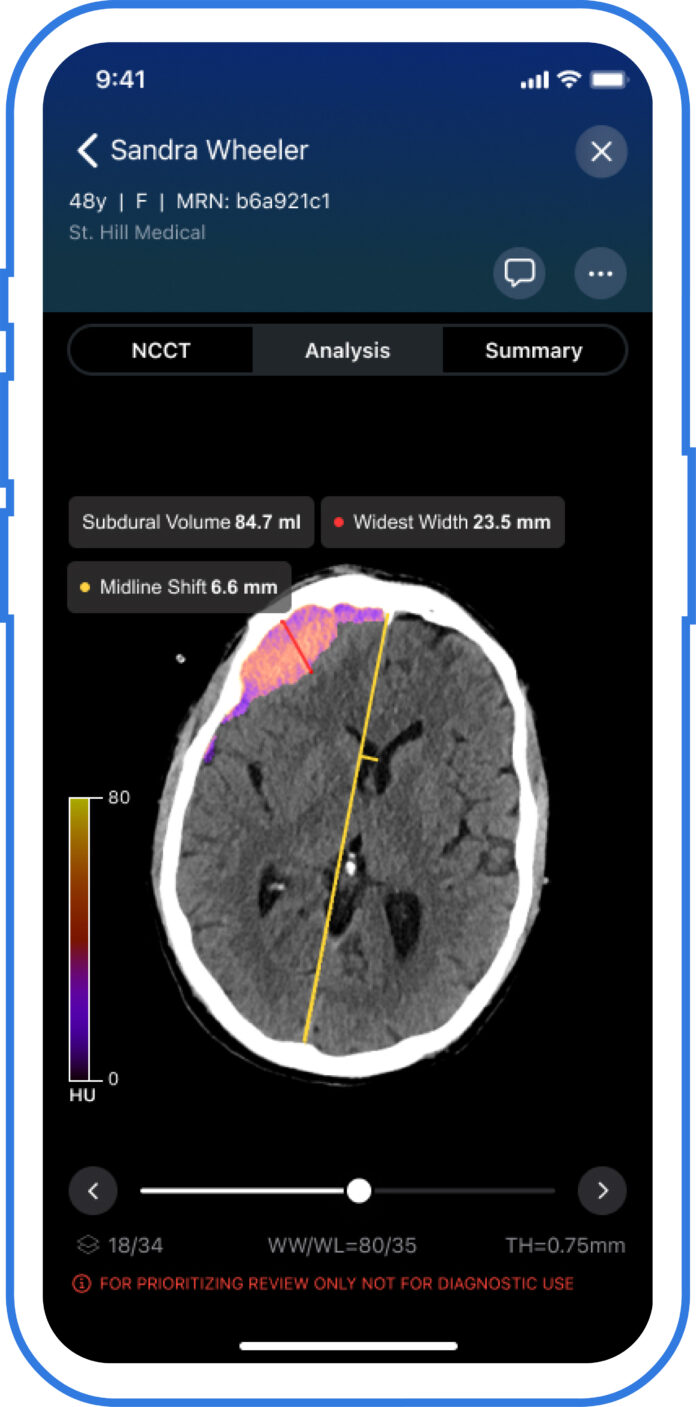

SAN FRANCISCO– Viz.ai has received FDA 510(k) clearance for its Viz Subdural Plus module, making it the first and only AI-powered solution approved for automatically measuring subdural hemorrhages on non-contrast CT scans. The breakthrough tool enables precise labeling, visualization, and quantification of subdural collections, helping physicians make faster and more informed treatment decisions.

Designed to operate within the Viz.ai One platform, Viz Subdural Plus streamlines a process that has traditionally required manual analysis by clinicians. The AI-powered module provides volumetric data, maximum thickness, and midline shift measurements directly from NCCT imaging, supporting faster diagnosis and treatment planning—particularly for patients with chronic subdural hematoma (SDH).

“Viz Subdural Plus introduces a new level of precision in diagnosing and monitoring subdural hemorrhage,” said Dr. David J. Altschul, Division Chief of Cerebrovascular Neurosurgery at Montefiore Health System. “Having automated volume and max thickness measurements at our fingertips allows us to make faster, more informed treatment decisions—especially critical in managing elderly patients or those on anticoagulants.”

The clearance comes at a time of growing clinical need. Chronic subdural hematomas are expected to become the most common cranial neurosurgical condition in adults, with projections estimating up to 60,000 new cases per year in the U.S. by 2030. The rise is linked to an aging population and increased use of blood-thinning medications. Quantifying the extent of subdural collections is vital for assessing severity, tracking changes over time, and determining treatment strategies, such as middle meningeal artery (MMA) embolization—a minimally invasive procedure increasingly used to prevent recurrence.

With Viz Subdural Plus, clinicians can eliminate the time-consuming and often variable manual measurement process. The tool fits into Viz.ai’s broader Viz Neuro Suite, which is currently used in more than 1,800 hospitals and health systems nationwide.

By combining advanced AI with real-time workflow integration, Viz Subdural Plus aims to reduce variability in care and enhance the precision of neurological treatment planning, particularly in urgent or complex cases.